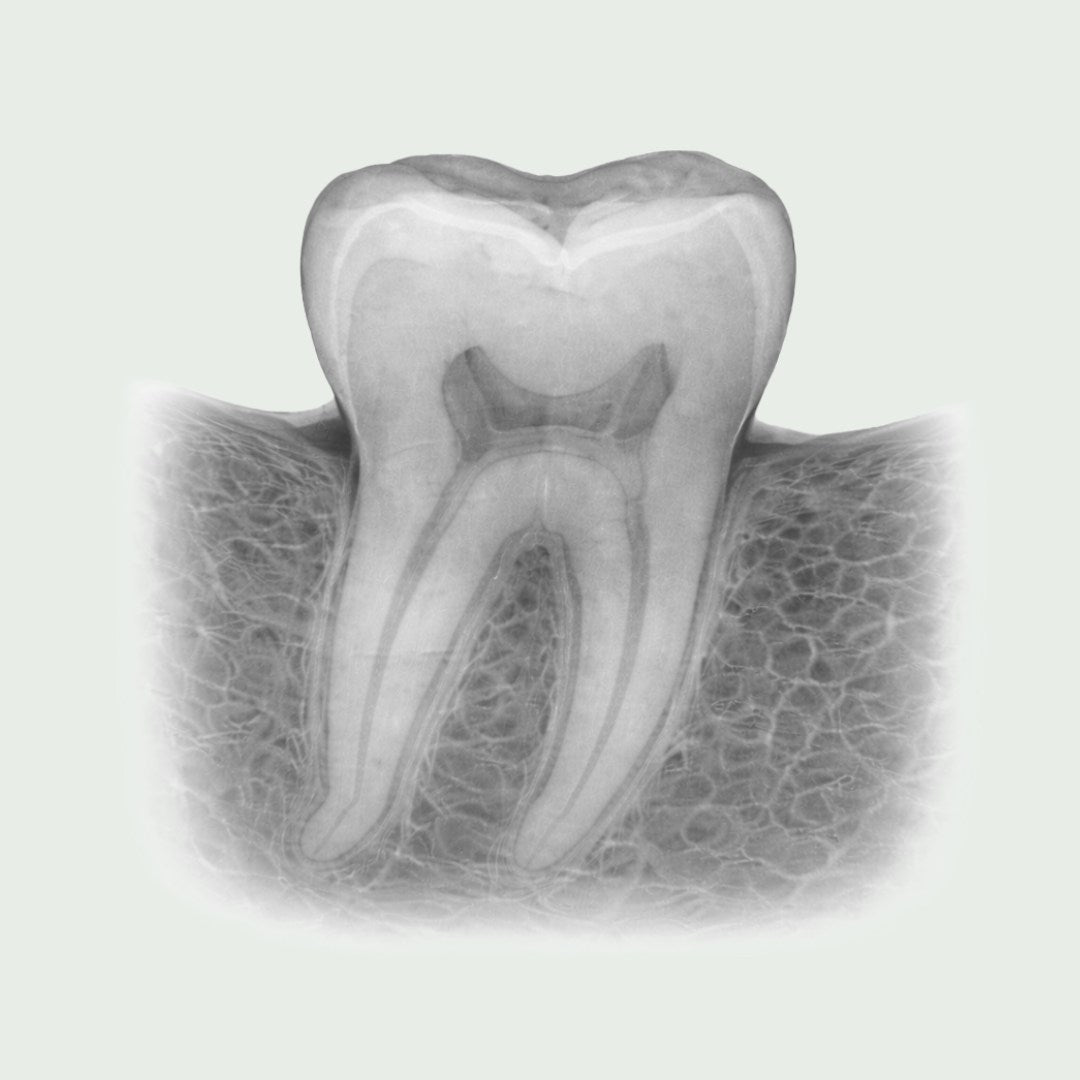

Digitale røntgenbilder er essensielt for presis diagnostikk og effektiv behandling. Vi bruker moderne røntgenteknologi som gir svært detaljerte bilder av tenner, tannrøtter, kjeveben og omliggende strukturer. Dette gjør at tannlegen raskt og nøyaktig kan identifisere problemer som karies, betennelser, infeksjoner og andre skjulte tilstander.

Digital røntgenskanning

Vi bruker avansert digital røntgenteknologi som sikrer detaljerte bilder med lav stråling, noe som gjør undersøkelsen trygg og komfortabel.

Digitale røntgenbilder gir tannlegen innsikt i din munnhelse som ikke er synlig ved vanlig undersøkelse. Disse bildene muliggjør tidlig diagnose, nøyaktig behandling, og forebygging av mer alvorlige problemer. Med minimal stråling og høy presisjon sikrer vi trygghet og gode resultater for din tannhelse.